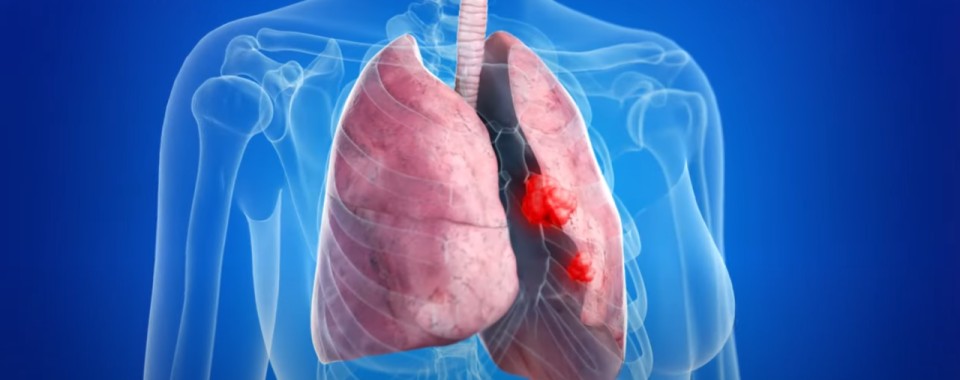

폐암 증상에는 기침, 체중 감소 흉통, 혈담 즉 피가 섞인 가래, 호흡곤란 등이 있지만, 위 증상은 다른 폐 질환에서도 나타날 수 있는 증상으로 구분하기가 어렵다. 그리고 폐암 초기에는 특별한 증상이 없는 경우가 대부분이라서 최근 흡연뿐 아니라 미세먼지 등 여러가지 요인으로 폐암이 발생하는 경우가 많아 정기검진으로 조기에 발견하는 것이 중요며 폐암 검진을 위해서는 특히나 저선량 흉부 CT를 촬영하는 것이 좋다라고 전문가들은 말하고 있습니다..